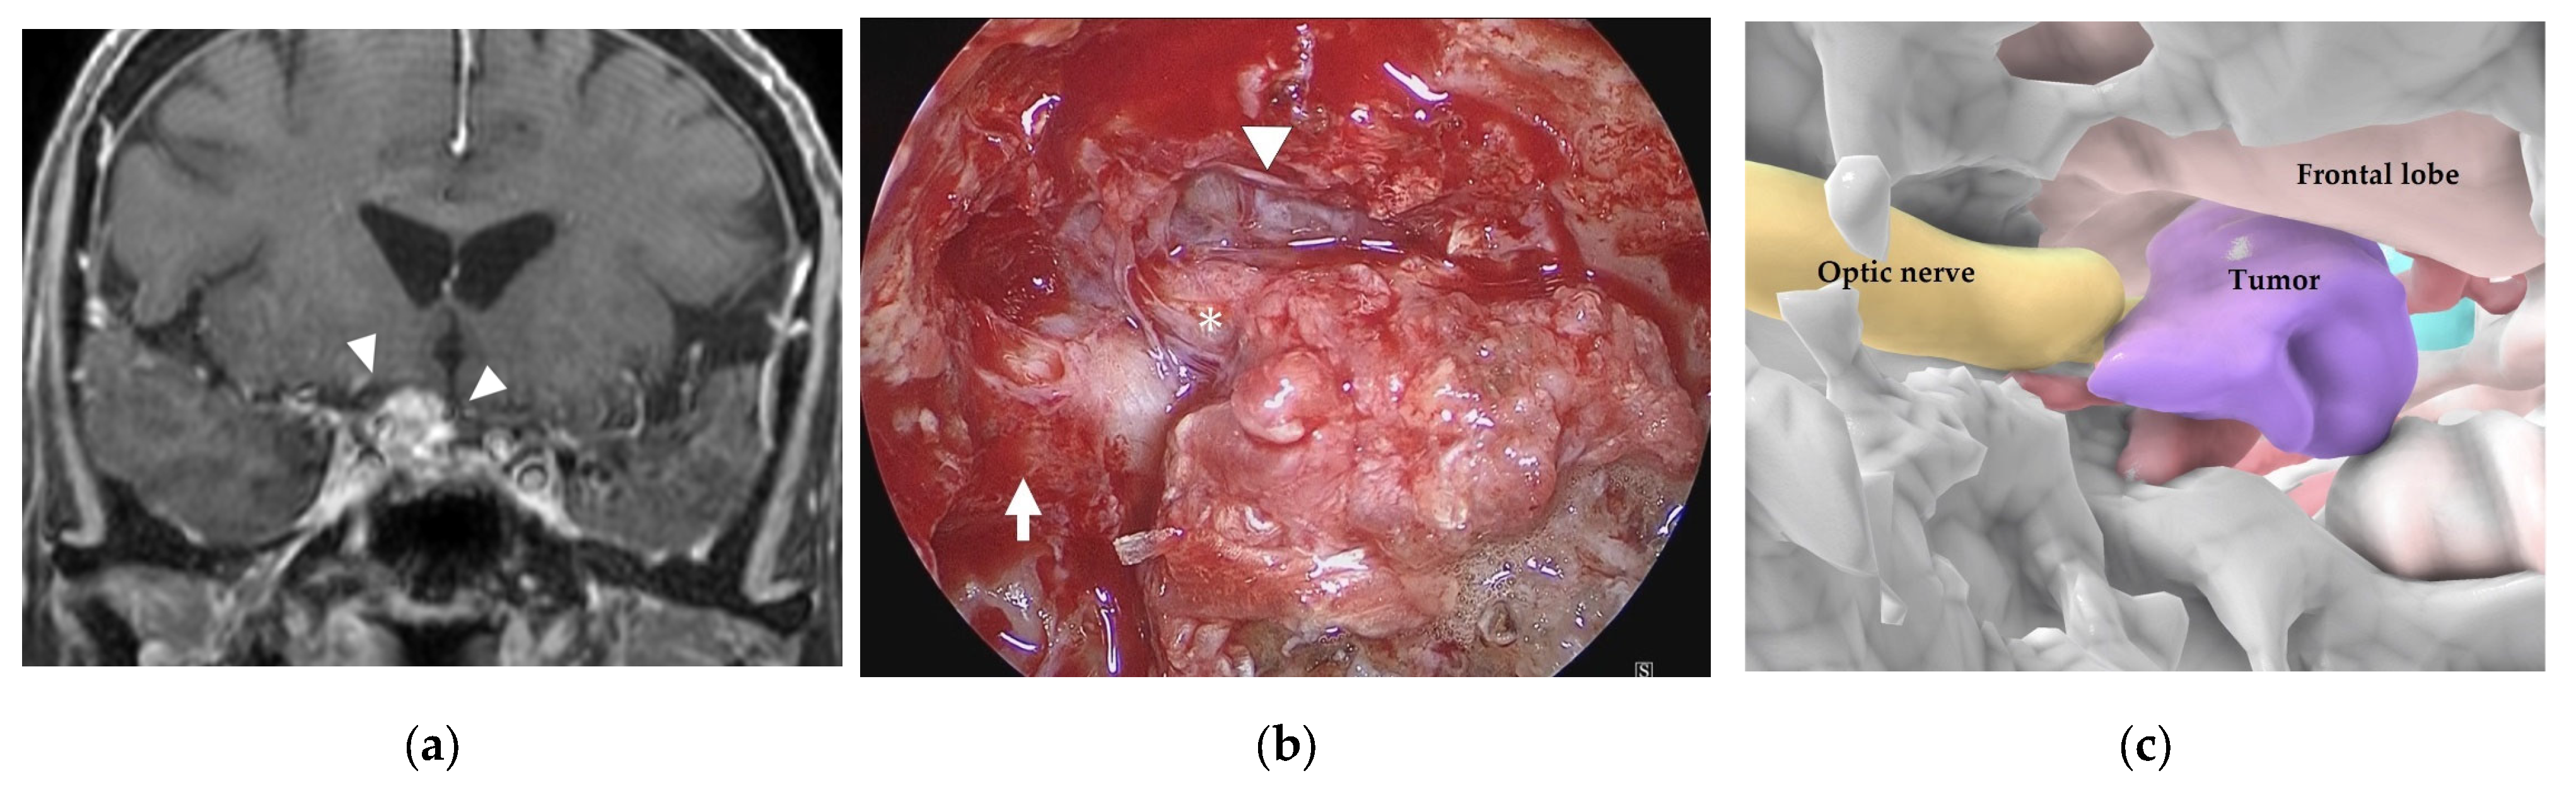

3.3. Illustrative Case 3 (Case 10)